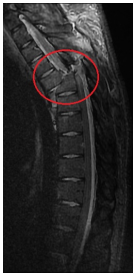

患者入住骨科后,因损伤重,失血多,血压低,考虑有“失血性贫血、低容量性休克、急性肾功能不全”,当日凌晨予急诊输血治疗,复查血红蛋白仅86.00g/L。颈椎核磁共振(MRI)证实“胸部脊髓横断伤(胸5/6平面)”,患者还合并“左6-8肋骨折、创伤性胸腔积液”,潜在肺损伤、胸腔积液随时加重可能,且存在压疮、肺部感染、深静脉血栓、尿路感染等高风险,病情危重、复杂。患者年轻,尽管脊髓横断伤,预后极差,但主管医师黄孝明主治医师仍尽可能想为患者尽早安排手术,依据病情需要,第一时间请口腔科、耳鼻喉科、胸外科、麻醉科等多学科MDT联合会诊,积极完善术前检查及准备,及时准备胸椎手术耗材,骨科医护团队尽早启动加速康复外科治疗(ERAS),积极防治肺部感染、压疮、深静脉血栓、营养不良、尿路感染、胃肠功能紊乱、便秘等并发症,同时加强患者及家属心理疏导。

在麻醉科、胸外科、输血科、重症医学科等多科室的配合下,患者于2024年07月18日由骨科吴俊一主任医师主刀、宿瑞强主治医师、黄孝明主治医师等配合下,在全麻下进行了“经后路胸6椎体骨折、胸5/6椎脱位切开复位胸3-8钉棒系统(8钉2棒)内固定术+胸5-6椎管扩大减压+硬脊膜修补术+自体骨、人工骨椎板后、关节突植骨融合术”。术前胸外科先行“双侧胸腔闭式引流术”。术后转入重症医学科重症监护治疗。术中使用了关键设备——超声骨刀,为脊柱椎管扩大减压大大节省了时间,止血彻底;术中同时使用了另一神器,可谓“千里眼”的“C臂X光机”,为手术安全性提供了强有力的保障。